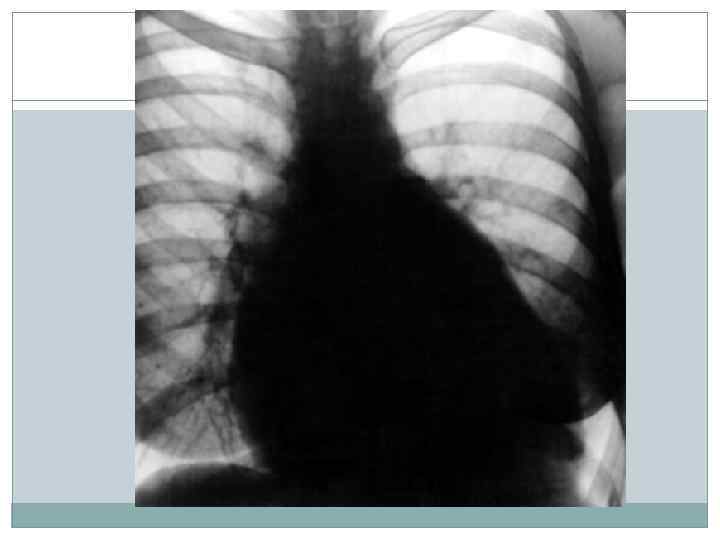

Рентгенография сердца в 3 -х проекциях- 1. Митральная конфигурация 2. Отклонение пищевода по дуге большого радиуса